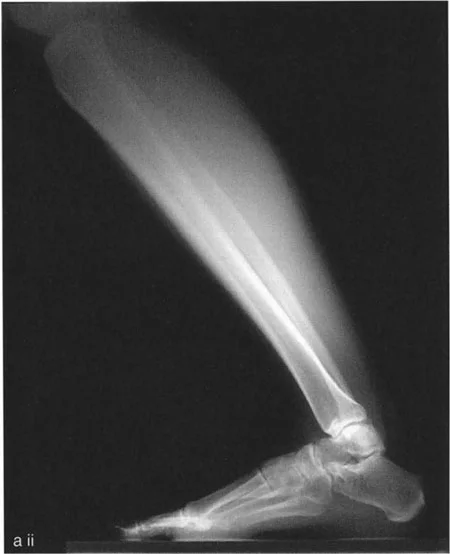

* الأشعة السينية (X-rays) الواقفة لكامل الطرف السفلي: هذه الأشعة ضرورية لتقييم المحاذاة الكلية للطرف السفلي تحت تأثير وزن الجسم. يطلب الأستاذ الدكتور محمد هطيف صورًا شعاعية كاملة الطول للساق أثناء الوقوف (Full-length standing alignment films) لتقييم المحور الميكانيكي للساق وتحديد زوايا المفاصل بدقة.

* الأشعة السينية الجانبية والامامية الخلفية للكاحل: تُظهر هذه الصور تفاصيل مفصل الكاحل نفسه، بما في ذلك زاوية القصبة الأمامية البعيدة (ADTA) وزاوية القصبة الوحشية البعيدة (LDTA)، وهي زوايا حاسمة لتحديد التشوه في المستويين الأمامي والسهمي.